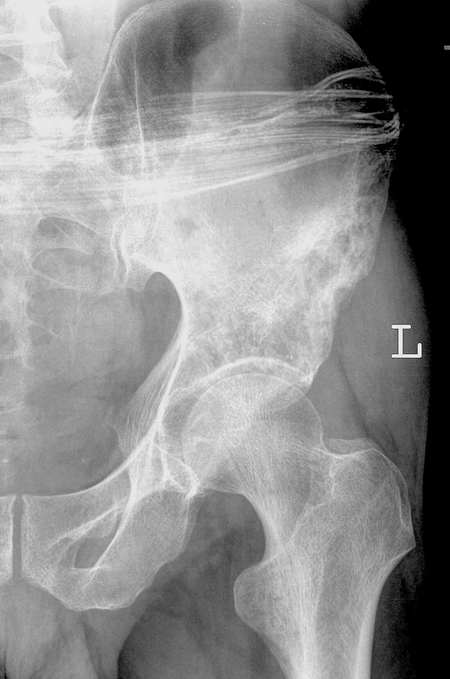

标题: X0455:骨盆,男45Y。

男,57,髋关节疼痛1年。

左髂骨内可见多发小透亮区,其内呈网格样,周边有硬化,骨皮质未见穿破,临近软组织内无肿瘤骨.

诊断:左髂骨血管瘤.

讨论:

骨血管瘤为原发于骨血管的良性肿瘤。组织学上可分为海绵状血管瘤和毛细血管瘤两型。前者,是由大的薄壁血管和血窦构成,其中充满血液,表面被覆一单层的扁平内皮细胞,好发生于脊柱和颅骨 。毛细血管型血管瘤,较少见,由极度扩张增生的毛细血管型构成,为柔软暗红色,好发于扁骨和长管状骨干骺端。

骨血管瘤的基本影像学表现:垂直型呈栅栏状或网眼状,为垂直排列的粗糙的小梁,是脊柱血管瘤典型x 线表现。由于椎体内松质骨结构吸收减少和消失,为适应力线,骨小梁代偿增粗,纵形排列,间以低密度间隙,呈栅栏状。ct 平扫,椎体松质骨呈粗大网眼状改变,残留骨小梁增粗,呈稀疏排列的高密度斑点,矢状面或冠状面重建图像呈栅栏状改变。偶而可见椎旁软组织肿块。日光型显示自板障伸出的太阳光芒状骨针,x 线正位片上自骨缺损区中央向周围放射状排列,切位片上显示病变膨隆,膨出部分可见与颅骨垂直的骨针,亦呈放射状。ct 除能显示以上征象外,并能显示肿瘤向颅内生长脑皮质受压内移。泡沫状多见于长管状骨和扁平骨血管瘤。肿瘤呈泡沫状溶骨破坏,患者局部呈梭形膨胀,周围皮质变薄,一般无骨膜反应 。

左髋关节内未见明显骨质异常,关节间隙也适中,边缘清晰,应该没什么问题。左侧髂骨外侧缘可见多发的小透亮影,边缘呈网格样硬化,考虑是血管瘤的可能性大,建议骨穿。